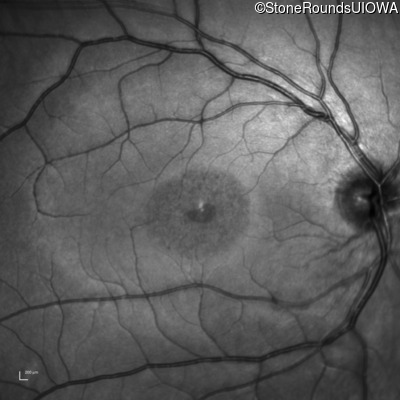

AR Stargardt Disease (IIA)

Age at visit: 18 years

AR Stargardt Disease ABCA4 Arg1108Cys CGC>TGC Val2114Val GTG>GTA AR